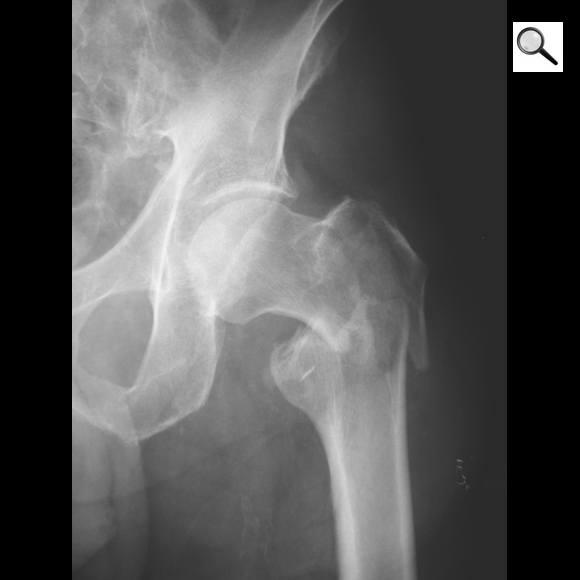

Quel diagnostic? Quel traitement?

Fracture inter-trochantérienne de l’ES du fémur gauche

ttt= vis plaque ou clou gamma